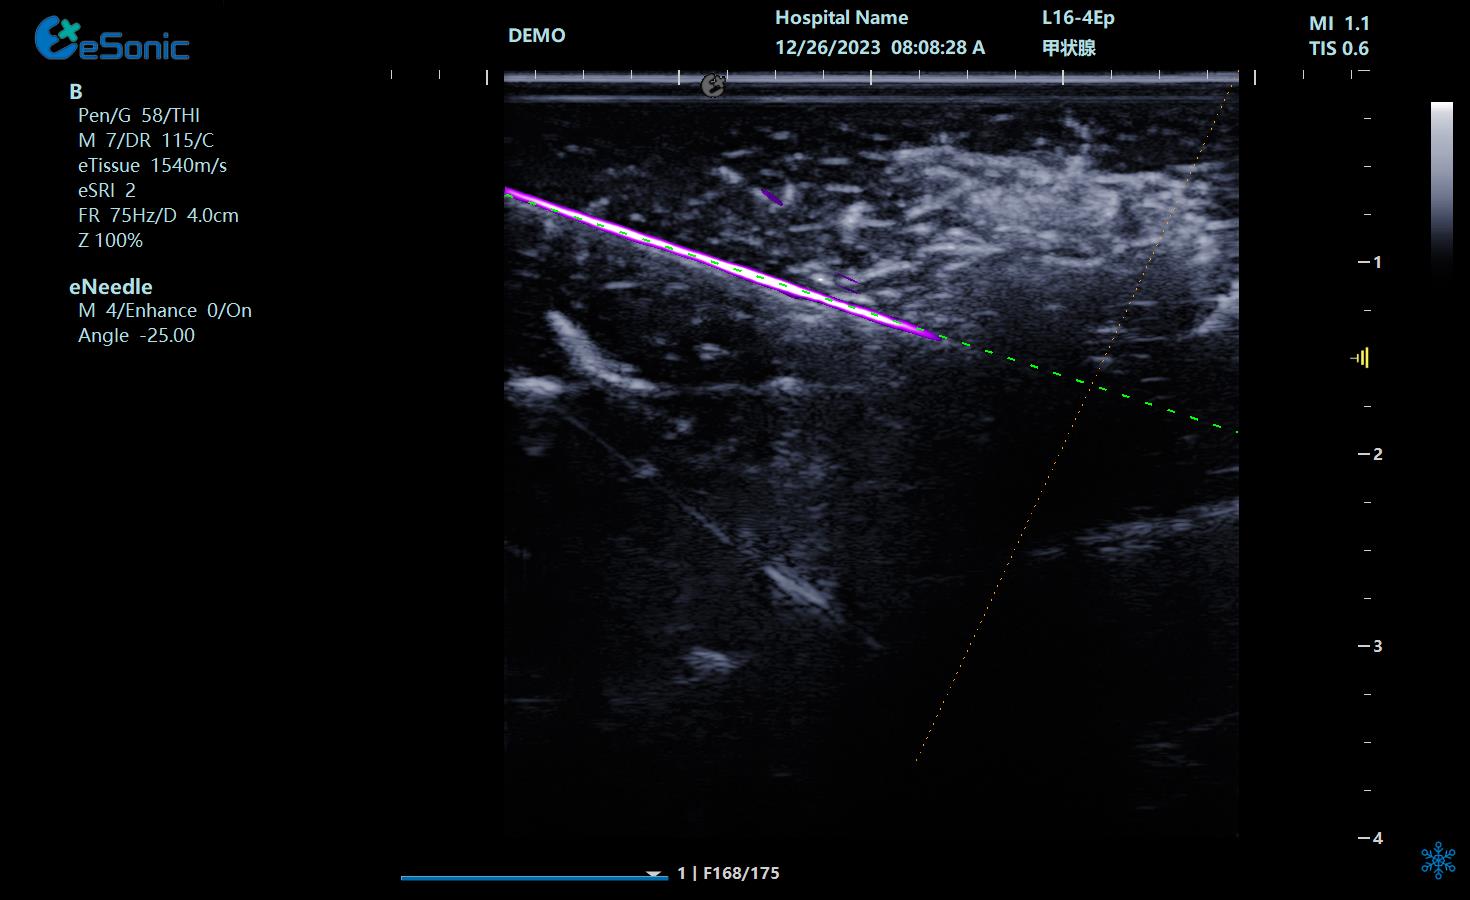

eHertz新技术助力急重症新突破 ---超声引导下的有创操作

超声引导下心包穿刺;胸腔积液及积气穿刺、置管;腹腔积液的抽取;CVC、PICC置管;超声引导下动脉穿刺;穿刺活检;ECMO;重症胰腺炎经皮穿刺置管引流;区域神经阻滞

肌骨领域超声引导介入治疗

穿刺针智能解决方案:穿刺针增强显影,智能MAP,无磁导航,为临床医生有创穿刺保驾护航,真正实现精准导航。